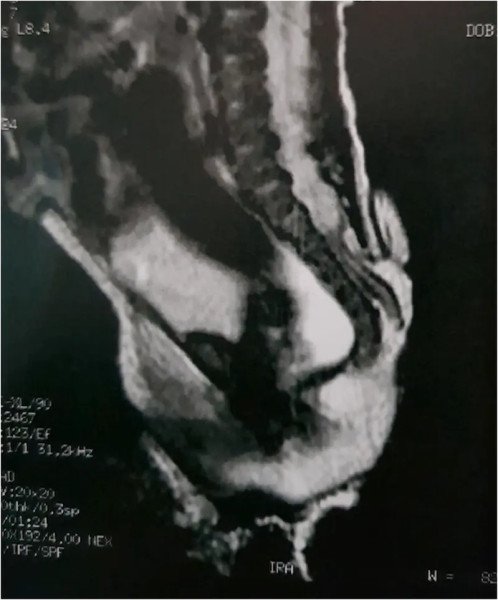

ولدت طفلة برازيلية بذيل يبلغ طوله 6 سم كان مغطى بالجلد وبارزاً من ظهرها، وقد تمكن الجراحون من إزالته في ظاهرة يطلق عليها "السنسنة المشقوقة" والتي تعتبر نادرة جداً بالحدوث.

ونشرت مجلة (Journal of Pediatric Surgery Case Reports) صوراً لا تصدق قبل الجراحة وبعدها، تُظهر الفتاة بعد 3 سنوات من العملية التي غيرت حياتها، وفق صحيفة "ديلي ميل" البريطانية.

في التفاصيل، ولدت الفتاة التي لم تذكر تقارير الجراحين هويتها، مصابة بـ"السنسنة المشقوقة"، وهي عيب خلقي نادر في العمود الفقري يحدث في الرحم، ويسبب فجوة في العمود الفقري. وفق (العربية نت)

وهذه الحالة هي نوع من عيوب الأنبوب العصبي، وهو بنية بالجنين النامي تصبح في النهاية دماغ الطفل والحبل النخاعي والأنسجة التي تحيط بهما.

فيما تمكن الجراحون من إزالة الذيل. وكشف الأطباء من مستشفى GRENDAAC للأطفال في ساو باولو، أن الذيل انتشر من المنطقة القطنية العجزية، وهي المنطقة التي تربط العمود الفقري بالحوض.

كما شخص الفريق هذه الأنسجة الزائدة على أنها "ذيل بشري زائف".

يشار إلى أنه تم تسجيل أقل من 200 حالة من هذه الظاهرة، وهي حالة غير طبيعية أثناء الحمل.